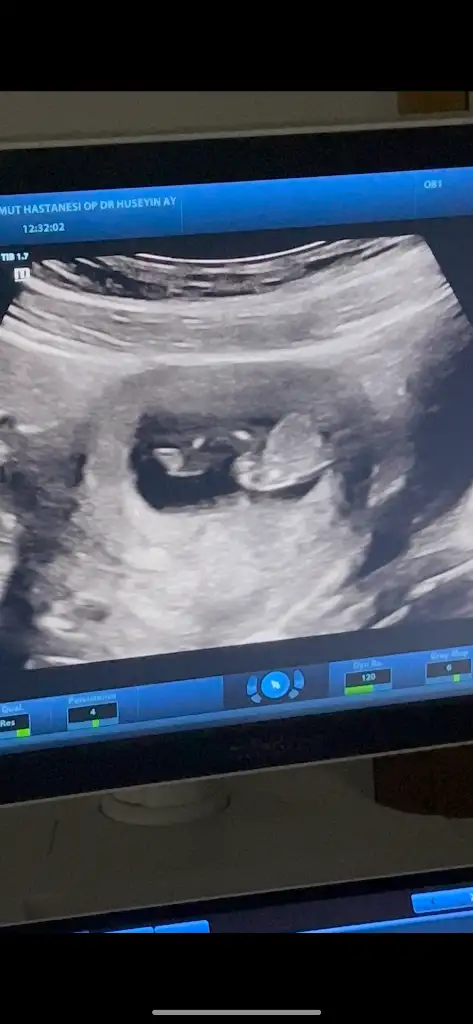

Bende çıkıntı gibi gördüm 19 haftada artık net bişey söylemesi gerekirdi19 haftalık doktor kıza benzetti ama bir cikinti var penise benzetmedim dedi

Benim 12 ve 13 haftalık görüntüye benziyor ama bana da kordon iki bacağının arasında yine de yüzde doksan erkek gibi dedi şu an 16 haftalık haftaya tekrar gidicem15+3 günlük doktor kıza benziyor dedi ama ben erkek görüyorom. Sizce?

13. Haftada da böyle göründü15+3 günlük doktor kıza benziyor dedi ama ben erkek görüyorom. Sizce?

Haber edin lütfen. 3 hafta sonra gel dedi bana. Bekleyelim bakalımBenim 12 ve 13 haftalık görüntüye benziyor ama bana da kordon iki bacağının arasında yine de yüzde doksan erkek gibi dedi şu an 16 haftalık haftaya tekrar gidicem

Foto net diğil. Amma erkek gibi hiss etdim. Sizde 16-haftamı burda?Benim 12 ve 13 haftalık görüntüye benziyor ama bana da kordon iki bacağının arasında yine de yüzde doksan erkek gibi dedi şu an 16 haftalık haftaya tekrar gidicem

Yok şu an yeni 16 hafta oldu. Resimlerdeki 12 ve 13 haftalık görüntüsüFoto net diğil. Amma erkek gibi hiss etdim. Sizde 16-haftamı burda?